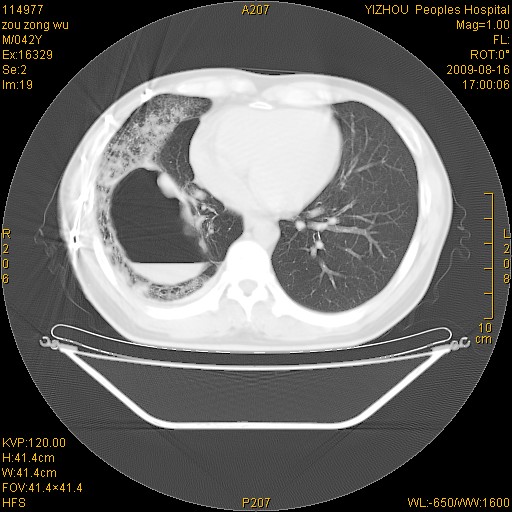

以下是引用zjzjr在2009-8-17 10:42:00的发言:[br]右侧间质性肺炎伴纤维化,右肺下叶肺囊肿伴感染(不除外外伤后引起),右肺野及胸壁软组织\\肝内见多发斑点状,中枪了吧.右侧胸膜肥厚\\粘连.